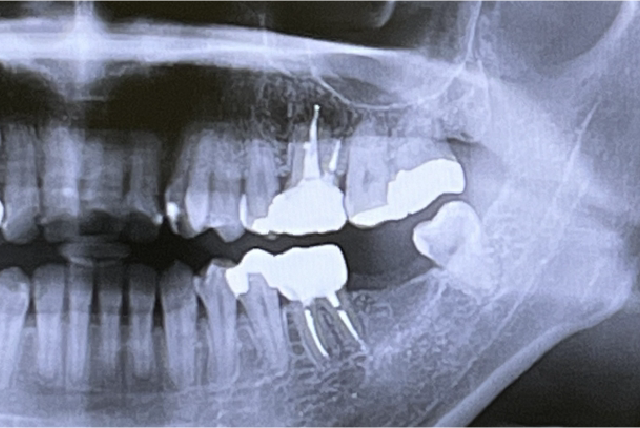

目で見えない部分の歯石の付着や、歯周病によって骨が影響を受けている部分をレントゲン写真により正確に把握することができます。